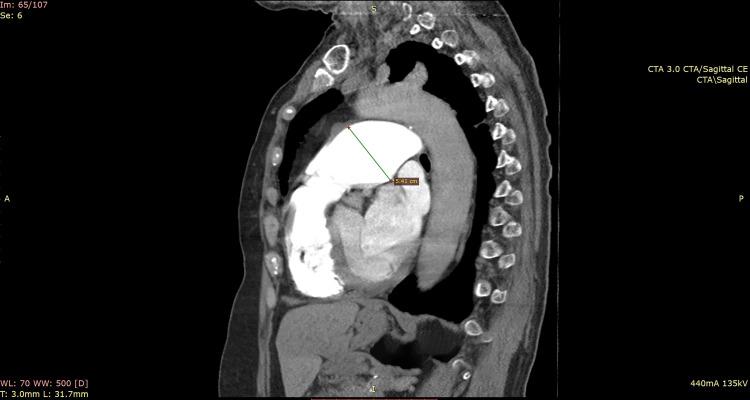

A Novel Approach for the Treatment of Pulmonary Artery Aneurysm Repair Using Inclusion Technique: A Case Report.

Right ventricle outflow tract dilatation and pulmonary artery aneurysm, rare cardiac conditions.

Symptomatic idiopathic pulmonary artery aneurysm: a case report and a mini-review of the literature.

Management of Giant Pulmonary Artery Aneurysm with Quadricuspid Valve Stenosis.

Improvement of lung function and pulmonary hypertension after pulmonary aneurysm repair: case series.

A Case of Preoperative Diagnosis of Pulmonary Artery Aneurysm Resected by Segmentectomy.

David's procedure for pulmonary artery aneurysm.